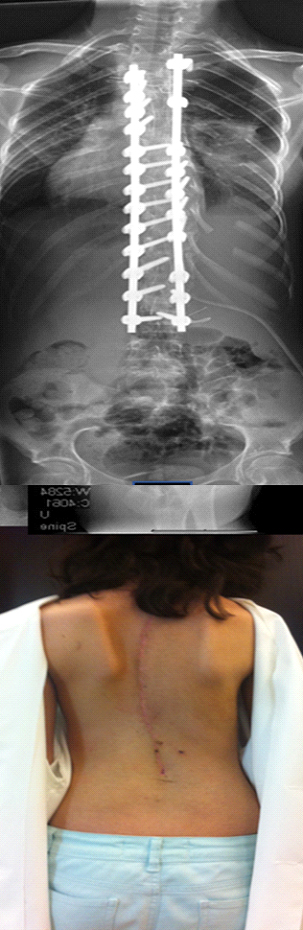

Вже багато років існують методики, що дозволяють позбутися помітних деформацій хребта. Існують клініки і досвідчені лікарі, які роблять успішні операції з корекції сколіозу з використанням спеціальних металевих конструкцій. Тисячі людей, зокрема діти, скористалися такою допомогою і тепер живуть повноцінним життям.

Який вид імплантів використовують для хірургічного лікування сколіоза?

Ця методика виключає травмування хребта, і хребет росте в правильному положенні. Жодного післяопераційного неврологічного порушення при цьому не відбувається – у більшості пацієнтів страх перед операцією на хребті пов’язаний саме з цим. Конструкція не травмує спинний мозок, вона дуже надійна, зроблена з надміцного інертного матеріалу – титану, який широко використовують в медицині.

Як швидко загоюється шрам після операції?